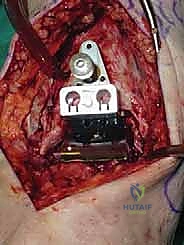

تتكون غرسة STAR من ثلاثة أجزاء رئيسية ولا تستخدم الأسمنت العظمي (Cementless)، بل تعتمد على النمو العظمي الدقيق داخل مسام الغرسة لتثبيتها بشكل دائم:

- المكون الظنبوبي (Tibial Component): صفيحة معدنية مسطحة من سبائك الكوبالت والكروم (Cobalt-Chromium)، تُثبت في أسفل عظمة الساق (الظنبوب) بواسطة أسطوانتين معدنيتين تدخلان في العظم لضمان الثبات المطلق.

- المكون الكاحلي (Talar Component): قطعة معدنية تغطي قبة عظم الكاحل، مصممة بشكل تشريحي منحني يحاكي تماماً شكل العظمة الأصلية، وتحتوي على أخدود طولي.

- الحشوة البلاستيكية المتحركة (Mobile Polyethylene Bearing): هذا هو سر نجاح غرسة STAR. هي قطعة من البلاستيك الطبي عالي الكثافة (UHMWPE) توضع بين القطعتين المعدنيتين. هذه القطعة ليست ثابتة، بل تنزلق بحرية للأمام والخلف، وتسمح بدرجة طفيفة من الدوران. هذا التصميم "المتحرك" يقلل بشكل هائل من إجهاد القص (Shear Stress) على واجهة العظم والمعدن، مما يقلل من احتمالية تخلخل الغرسة (Loosening) على المدى الطويل، ويمنح المريض نطاق حركة فسيولوجي مذهل.